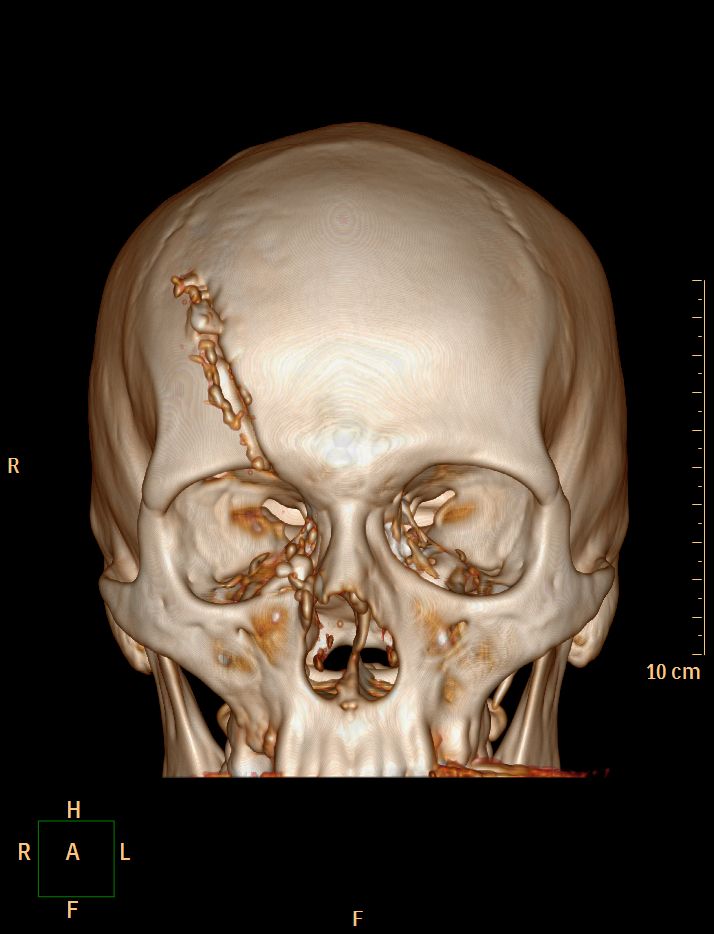

Accident de scie circulaire